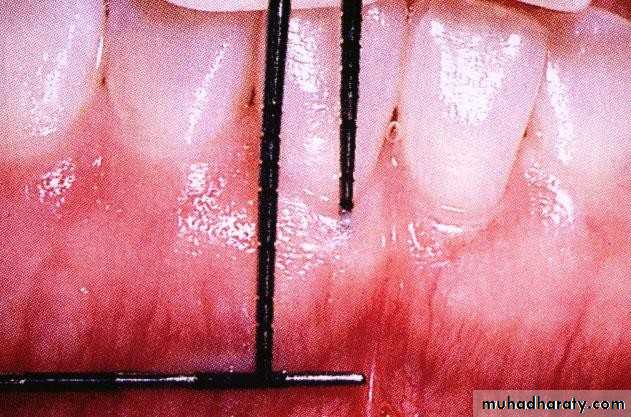

• Periodontal Examination

• Muccogingival Assessment

• Marginal tissue recession and lack of keratinized gingiva on Mandibular anterior teeth.

• Miller’s Classification of

Marginal Tissue Recession• Periodontal Examination

• Muccogingival Assessment• Measuring the width of Attached gingiva

• Periodontal Examination• Muccogingival Assessment

• Site with inadequate Attached gingiva (arrow)